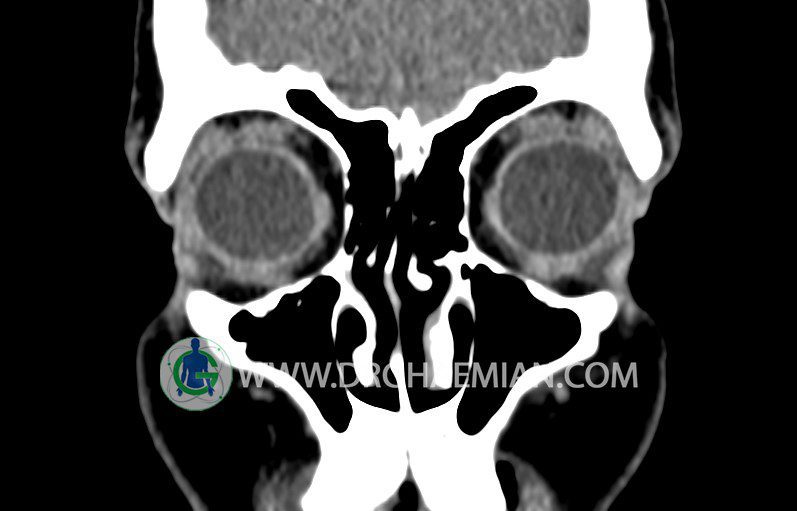

در HRCT اسپيرال از سينوس هاي پارانازال مقاطع کرونال و آگزيال ( 16 اسلايس و مقاطع ظريف 1.5 mm بدون فاصله ، با پنجره استخواني و نسج نرم ) :

– کونکا بولوزا در کونکای ميانی چپ و